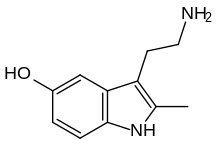

| 2-Methyl-5-hydroxytryptamine | artificial | 2-CH3, 5-OH | H | H | 3-(2-aminoethyl)-2-methyl-1H-indol-5-ol | 78263-90-8 |